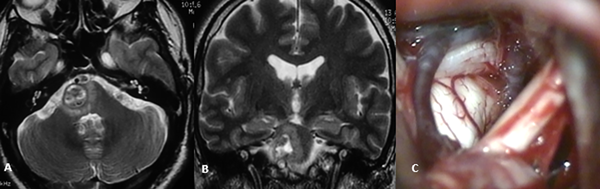

De igual forma, y ampliamente descriptos, los puntos de ingreso seguros (“safe entry zones”) al tallo encefálico son la zona anterior en el mesencéfalo, delimitada medialmente por el núcleo y trayecto del tercer par craneal, y lateralmente por el tracto corticoespinal, punto de entrada en uno de nuestros abordajes. También puede usarse el surco mesencefálico lateral. El mesencéfalo dorsal puede ser abordado a través de la región intercolicular, punto de acceso utilizado en dos de los casos descriptos en este artículo (Figura 2).12-14

Figura 2: RM ponderación en T2, proyección axial (A) y coronal (B) donde se evidencia cavernoma Zabramski II localizado a nivel del puente, lateralizado hacia la derecha. Imagen intraoperatoria de mismo paciente (C) con evidencia de lesión en contacto con superficie pial del tronco cerebral; abordaje retrosigmoideo.